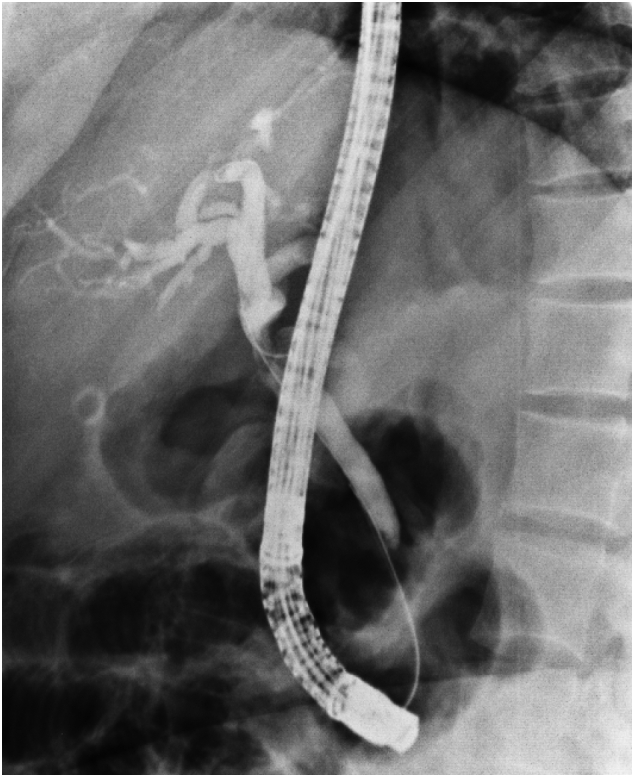

Computed tomography (CT) scan with contrast of chest and abdomen and pelvic showed enhancing soft tissue lesion in the porta hepatis with no evidence of distant metastasis. ERCP [Fig. 3] was done, showing a common hepatic duct stricture extending to just below the hepatic confluence. Brush cytology was done; however, no specific pathology has been identified, and a plastic stent was inserted for biliary decompression.